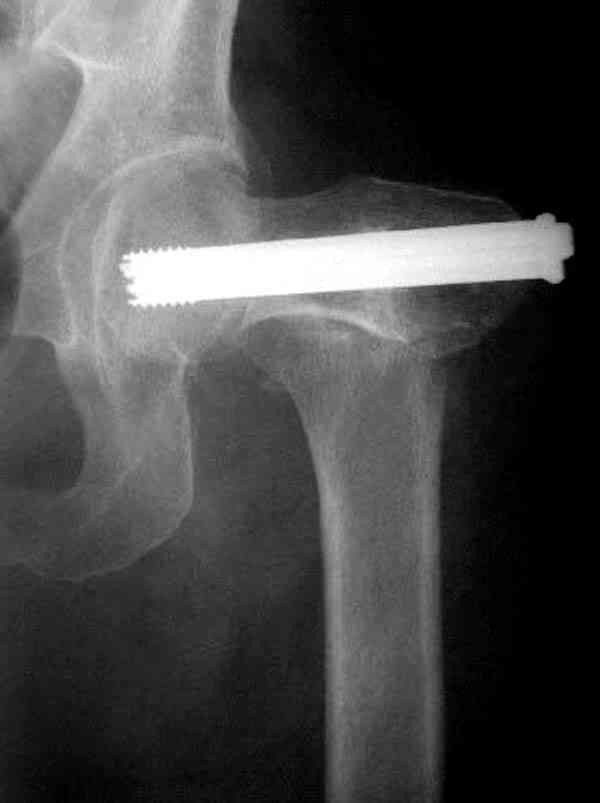

На Московской конференции в ноябре была продемонстрирована удивительная методика профилактического армирования шейки бедра у пациенток с остеопорозом и переломом контрлатеральной шейки в анамнезе.Странно, но дискуссии это сообщение не вызвало.Кто что думает об этом?

Спасибо, Антон. Я автор того сообщения по профилактическому армированию шейки бедренной кости, которое прозвучало на конференции, посвященной 50-летию создания АО. Мне тоже хотелось услышать вопросы по теме. Мы травматологи-ортопеды в первую очередь хирурги, а не терапевты. Почему в вопросе профилактики и лечения остеопороза мы ограничиваемся только консервативными методами лечения? Как можно практически научить больного не получать травмы, когда немало случаев возникновения переломов даже в постели. Первоначально идея армирования ШБК многих, при ком я озвучивал ее, шокировала, затем возникала дискуссия и большинство поддерживали эту идею. Мне бы очень хотелось развернуть дискуссию на странице этого сайта.

Кликните для загрузки файла P3230006.JPG

54KB (56062 bytes)

Отправитель: Анатолий Матвеев 22 Январь 2009, 18:11

Уважаемый Антон! У меня было всего три клинических наблюдения, снимки были продемонстрированы на московской конференции. Количества этих снимков хватило для подачи заявки, а затем и получения патента на изобретение. В свое время РОСПАТЕНТ потребовал подтверждения методики клиническими наблюдениями. У одной из больных действительно произошла повторная травма, и произошел подвертельный перелом на стороне армированной шейки бедренной кости (см. снимки). Это подтвердило основную идею изобретения - была сохранена и головка, и армированная шейка бедренной кости. Но тут не обошлось безпроблем. Анестезиологи отказались давать наркоз, а провести остеосинтез под м/а пластиной и винтом DHS не согласилась больная. Дальнейшее лечение скелетным вытяжением. На контр. Рентгенограмме через 2 месяца признаки формирования костной мозоли. Повторных обращений двух других пациентов не было. Для более детальных исследований и выводов необходимо значительно большее количество клинических наблюдений. Такие исследования могли быть проведены в условиях клиник медуниверситета. Напомню, я работаю в травмотделении провинциальной городской больницы. Насчет экспертов страховых компаний, так пусть они выскажут свое мнение. Армирование кости - это плановые операции по желанию больного, какие здесь могут быть противоречия? На армирование все больные, к моему удивлению, согласились довольно легко и сразу, поэтому остеосинтез и армирование были проведены в течение одной операции. С уважением А.М.